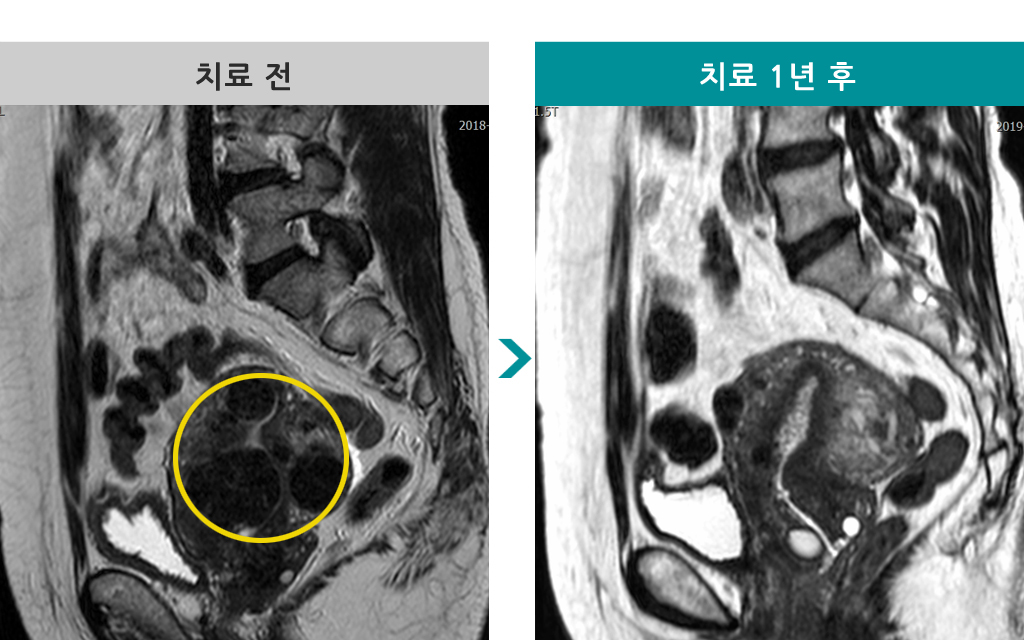

43세 [자궁근종 색전술] 전후 MRI사진 비교 - 자궁근종 배출(수술 효과)